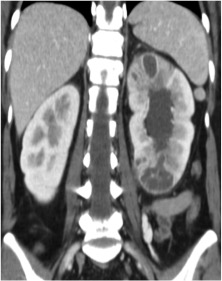

Se procede a realizar TC abdomino-pélvico con contraste en fase nefrográfica y excretora:

Conclusión: se nos presentó un caso de un paciente con una sospecha de infección renal complicada ya que tras cuatro días de tratamiento antibiótico no hubo mejoría. Ante los hallazgos observados en TC, podemos establecer el diagnóstico de pieloureteritis renal izquierda con signos de hidroureteronefrosis leve hasta vejiga.

B- Con el TCMD con contraste en fase excretora podemos estudiar las vías de manera más prescisa y hacer reconstrucciones. Estudio normal.

C- UIV de una hidroureteronefrosis izquierda leve (grado II/IV) hasta vejiga.